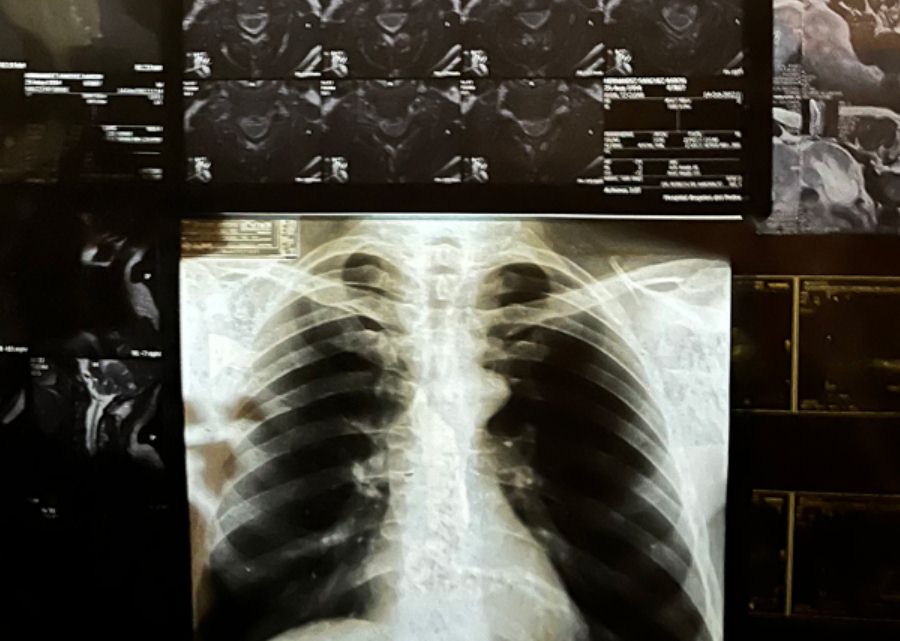

Una radiografía puede revelar la trayectoria vital del cuerpo, la historia vivida y lo que aún le aguarda. Tras una experiencia personal, Héctor de Anda (Jalisco, 1950) recurre a este material para elaborar sobre su relación con la enfermedad y el deterioro del cuerpo. Destinadas a un uso privado y a conservarse en un expediente médico, el artista las reutiliza para componer un dibujo configurado por recortes corporales (huesos, tejidos) que flotan en el vacío. No están agrupados según el donante o bajo ningún otro orden lógico: lo único que los une es que son fragmentos internos de origen humano.

En “Autoradiográficas”, el artista presenta una intervención a la estructura del museo para configurar un dibujo-vitral de nuestro propio interior. Hay un dolor latente en este collage intuitivo y visceral. Esta obra toma como punto de partida la frialdad y objetividad de la imaginería de las ciencias, haciéndolas retornar como huellas de marcas y heridas personales. Se vuelcan angustias y miedos; pero, sobre todo, esta pieza nos confronta con la inminencia del desgaste humano, recordándonos que estamos siempre expuestos a desgarrarnos, rompernos y enfermarnos.